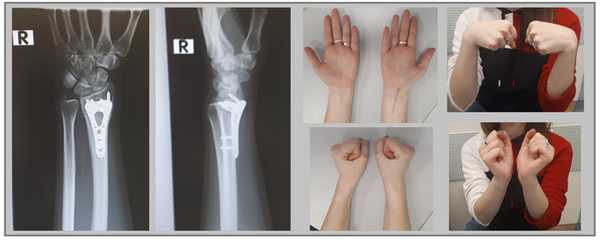

Например у Пациентки А, 24 лет, операция выполнена по поводу относительно простого перелома дистального метаэпифиза лучевой кости с угловым смещением к тылу на 30 градусов и укорочением лучевой кости на 7 мм. Учитывая молодой возраст и высокие функциональные запросы принято решение о выполнении остеосинтеза. Учитывая сохранность волярного кортекса использована пластина меньшего размера, которая установлена более проксимально, с целью максимального сохранения кровоснабжения эпифиза лучевой кости.

Через 6 недель наблюдается рентгенологическое сращение перелома. Функция конечности к этому времени уже практически полностью восстановлена.

В случае дистальных переломов, расположенных ближе к лучезапястному суставу, может возникнуть необходимость расположить пластинку ближе к суставной поверхности. Для этого лучше использовать специальную пластинку VA-LCP™ Volar Rim Distal Radius Plate.

Клинический пример. Пациентка С. 36 лет, травма при падении во время матча по большому тенису, получила закрытый оскольчатый перелом дистального метаэпифиза лучевой кости с большим количеством мелких фрагментов в метафизарной зоне.

На 7 сутки после получения травмы пациентка обратилась в Клинику К+31, учитывая нестабильный характер перелома предложено оперативное вмешательство. Для остеосинтеза использована пластина VA-LCP™ Volar Rim Distal Radius Plate.

Такая фиксация даже при таких тяжёлых дистальных переломах позволяет начать раннюю активизацию, занятия лечебной физкультурой в кратчайшие сроки после операции. Для профилактики КРБС при тяжёлых оскольчатых переломах рекомендуется использование витамина С в дозе 200 мг в сутки до 45 дней после травмы, возвышенное положение конечности в покое, хивамат, гипербарическая оксигенация, использование таких препаратов как актовегин и трентал.